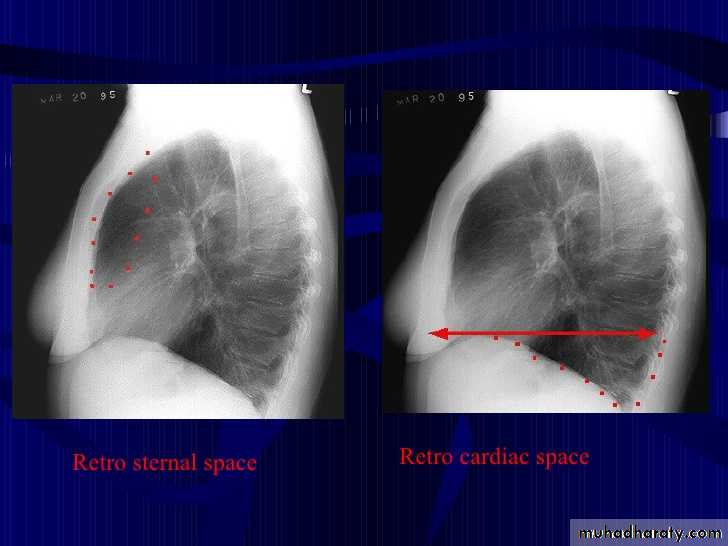

On lateral projections the left lower lobe is hyperexpanded and the oblique fissure displaced anteriorly. There is associated increase in the retrosternal opacity.